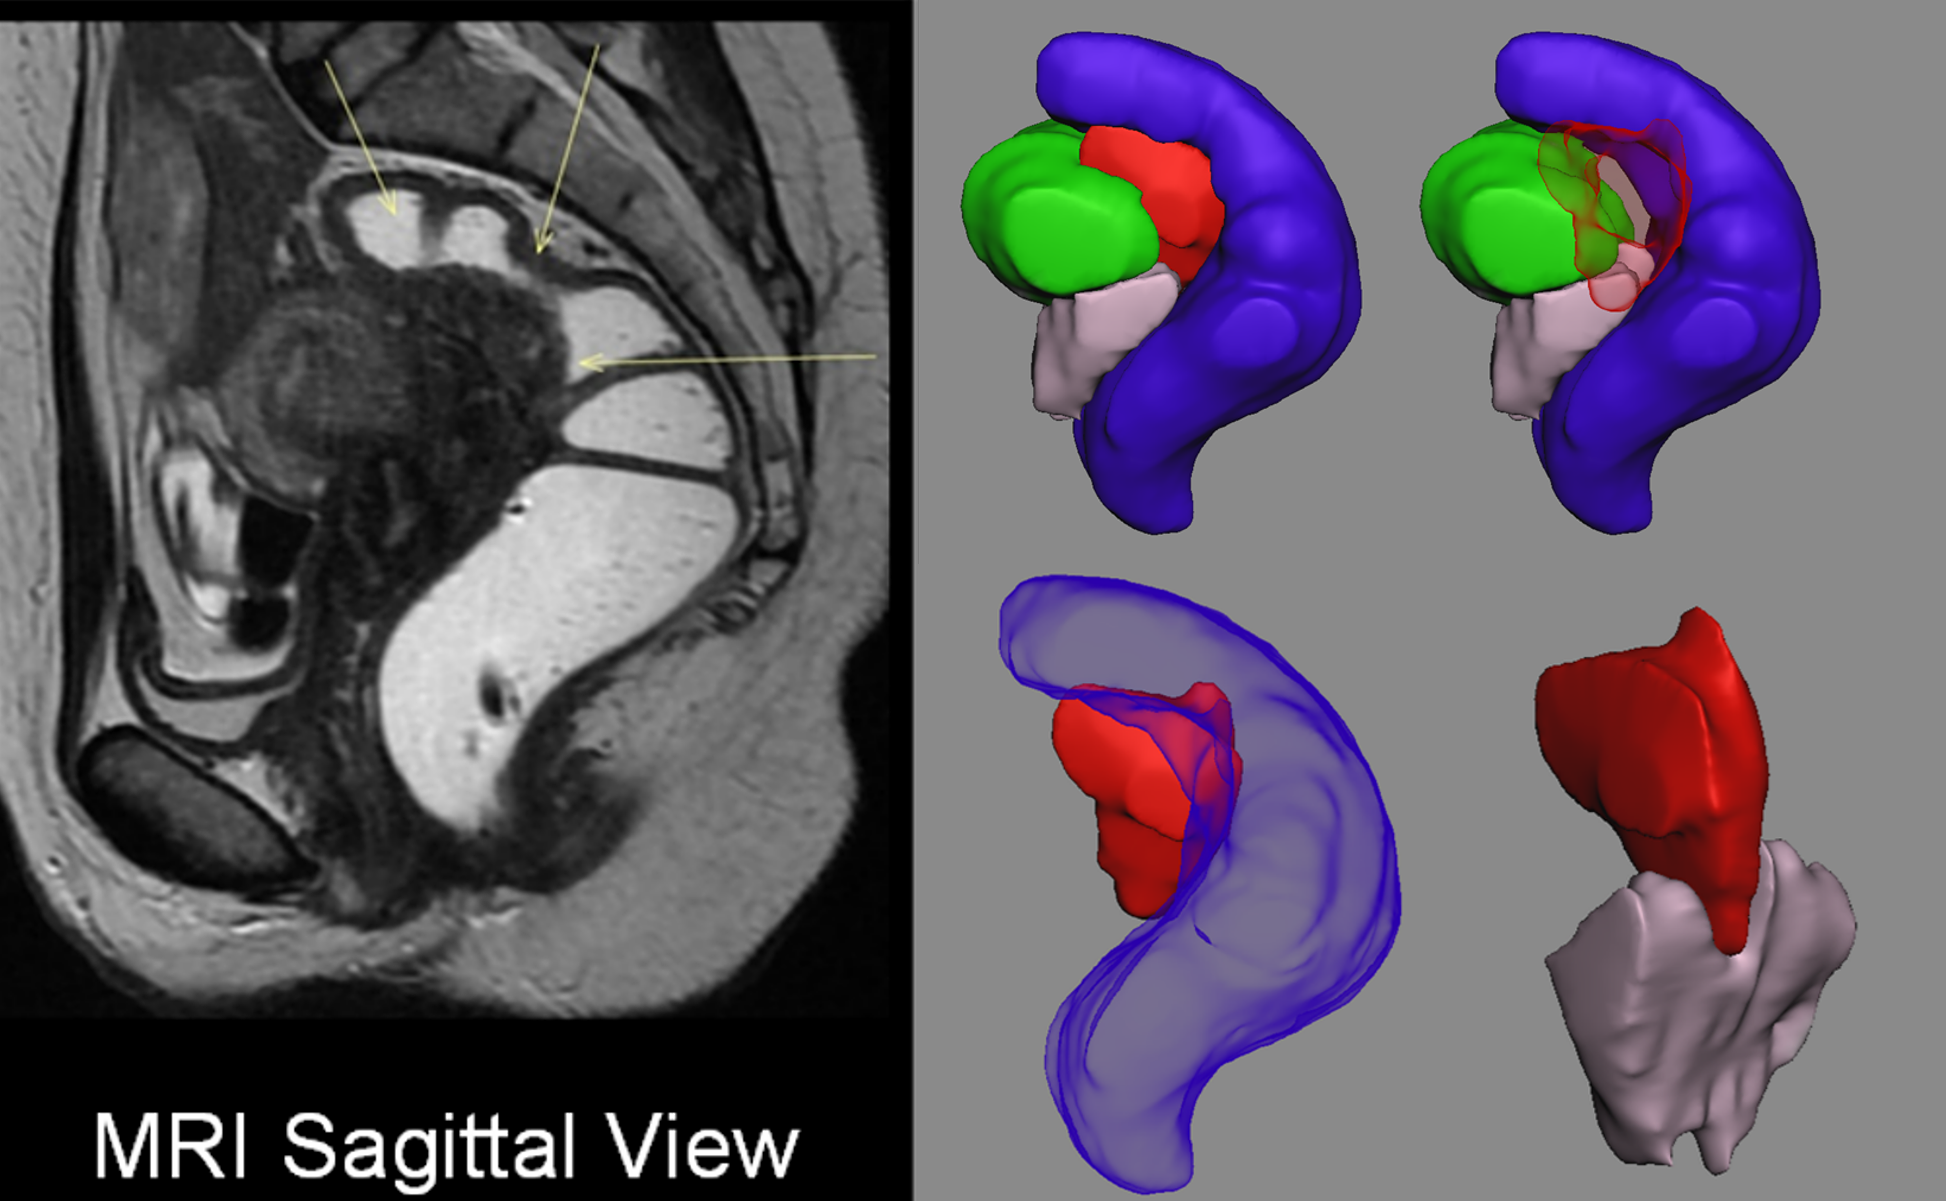

Pre-operative planning of deep posterior endometriosis cases